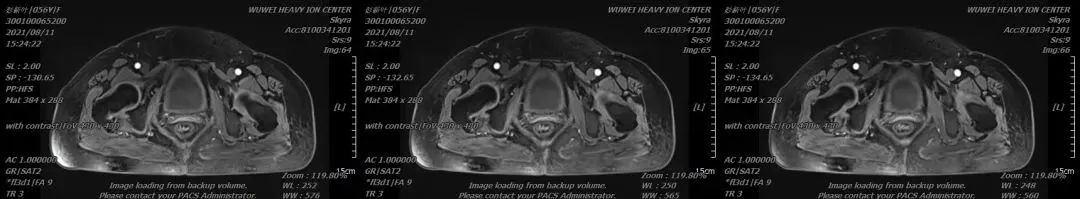

2021年03月重离子治疗前MR